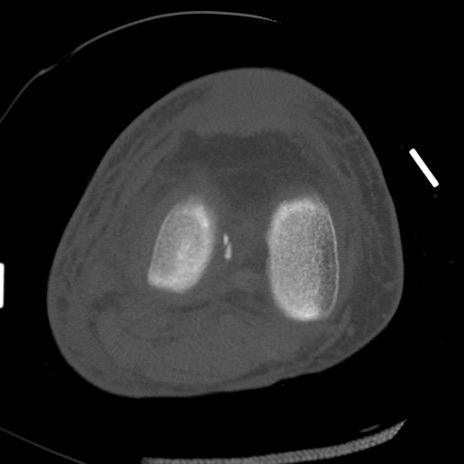

症例28 右膝関節CT(横断像)

右膝関節CT